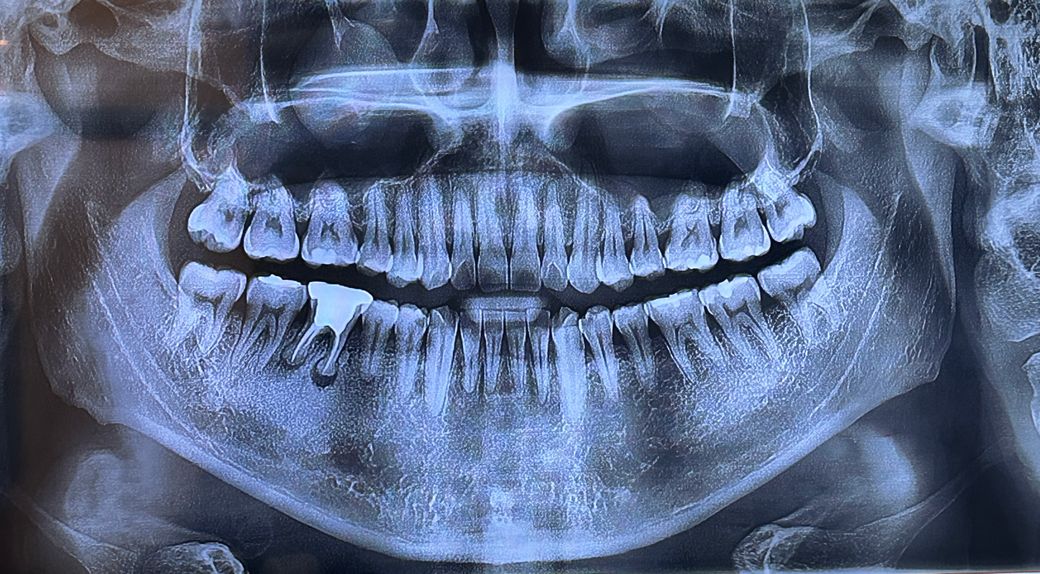

이정도면 뼈이식이필요한가요? 오늘 임플란트날입니다

이전과 비교입니다 처음상태에서 발치하고 3개월 후 오늘 임플란트날인데 뼈이식을 해야할거같다고하셔서 궁금합니다 사진 첨부합니다

• 사진상으로는 경계에 위치하는 것 같습니다. 뼈이식을 할 수도 있고 안할 수도 있어보입니다.

상태를 직접 본 선생님이 더 정확한 진단을 내리셨을것으로 봅니다.

• 안녕하세요 치과의사 김철진입니다. 저정도 상태라면 뼈이식을 특별한 이유가 없다면 하지 않고 바로 임플란트를 식립해도 될것같습니다.

• 파노라마 사진은 2차원 사진이고 정확한 판단을 위해서는 ct를 찍거나 수술하면서 직접 눈으로 봐야 합니다.

아래 사진이 발치 직후 사진이라면 현재(3개월 후)는 또 변화(발치 부위 잇몸뼈가 차오르는) 가 있을 것입니다.

• 임플란트를 식립하기에 잇몸이 약하고, 치조골이 부족한경우에는 뼈이식이 필요로 됩니다. 우선 뼈이식을 하고, 임플란트를 하는 것이 임플란트 성공을 높일수 있기에 뼈이식을 하길 권합니다.

• 발치를 하고 난 이후에 바로 식립을 한다면 빈 공간이 많습니다. 임플란트를 식립하고도 발치를 한 부위의 뼈가 아직 차오르지 않은 부위가 많으므로 해당 부위 등에 뼈 이식을 해야할 가능성은 높습니다. 따라서 현재 사진으로 보았을 때는 가능성이 높아 보입니다.